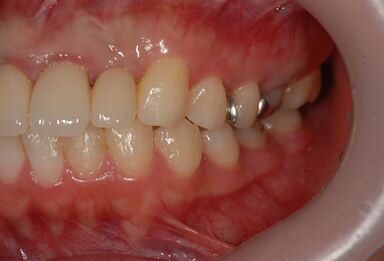

治療後

• 治療後